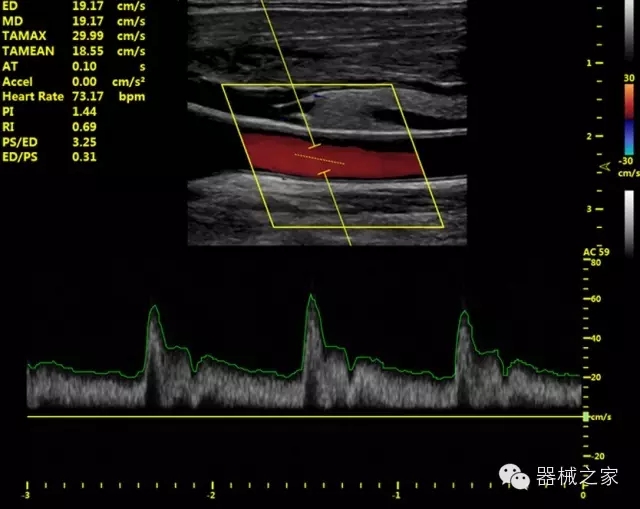

·獨(dú)有的HoloTM PW 實(shí)時3取樣門PW成像技術(shù),精確進(jìn)行血管診斷;

·一鍵優(yōu)化B、Color、PW,Auto Doppler自動識別血管位置、偏轉(zhuǎn)角度等,提高工作效率;

·30°超廣角精細(xì)偏轉(zhuǎn)成像技術(shù),更優(yōu)異的頻譜圖像;